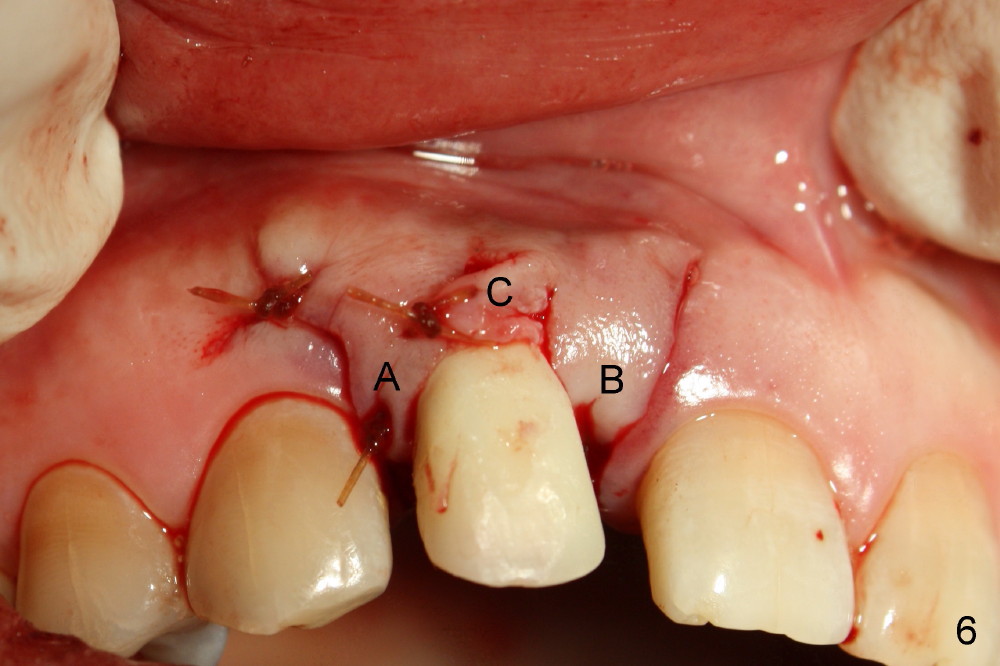

To increase buccal soft tissue bulk, the transverse incision is made lingual to the original socket (Fig.2 *). When the flaps are raised, the alveolar ridge appears to be deviated buccally; the implant (3.8x14 mm, insertion torque ~ 35 Ncm) also looks to be tilted too buccally even though it is placed in the middle of the ridge (Fig.3). An angled abutment (3.9 mm, 25º, 2 mm cuff, Torx A) has been adjusted buccally (Fig.4). The immediate provisional looks long (Fig.5). When the buccal flap is modified (Fig.5 insert) and sutured (Fig.6), the provisional looks to be tilted buccally. A custom Zirconium abutment should be used later on. All of these difficulties are due to delayed implantation with bone atrophy and are avoidable using immediate implant technique. Or check occlusion at the initial stage of osteotomy.